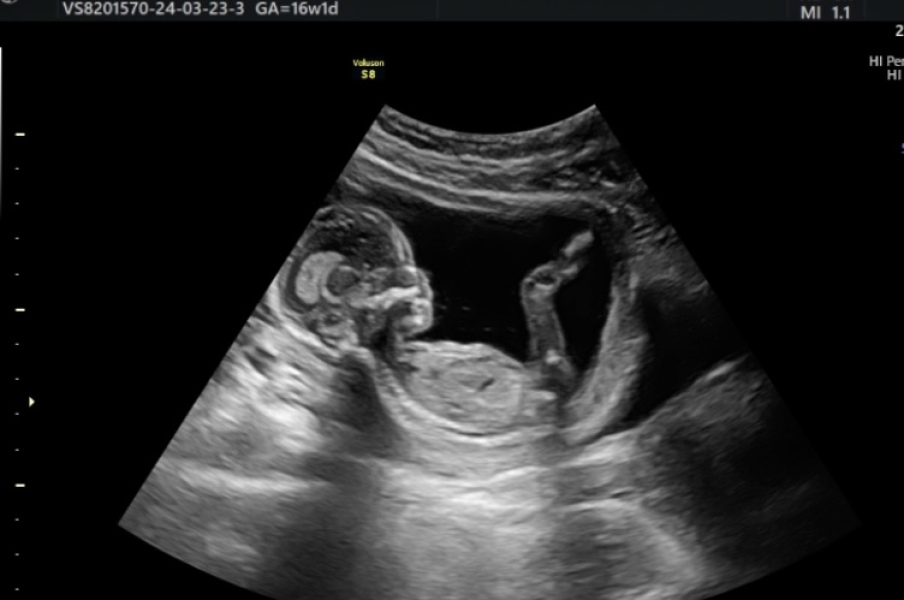

RachSmile · 23/03/2024 15:28

Had a private scan today at 16w1d… and it’s a girl! Took almost half an hour of the woman prodding at my stomach and making me go pee twice to get the baby to move as she was sitting with the cord between her legs so we couldn’t get a clear view straightaway 🤣 we had a gut feeling it was a girl and everyone in our family that knew about the pregnancy was convinced as well 💕 she has very long legs already that are measuring ahead - she’ll get that from her dad who is over 6”4!